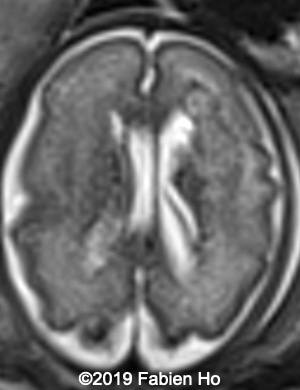

Images 4-11, fetal brain MRI at 28 weeks: the left frontal lesion hence shows DWI hyperintensity, with T2* and T1 peripheral hyperintensity: ischemia with peripheral subacute hemorrhage. Note also that there is an associated blood clot in the left lateral ventricle. There is no obvious mass effect, nor peripheral edema. All these findin>gs are very suggestive of a clastic lesion.

Axial T2*w: T2* sequence is used in this case for its susceptibility to magnetic field inhomogeneity, i.e. to iron deposits for example. It is used to depict hemosiderin, which is roughly oxidized blood, i.e. “aged” blood. Blood MRI signal evolves as time passes.

6

7